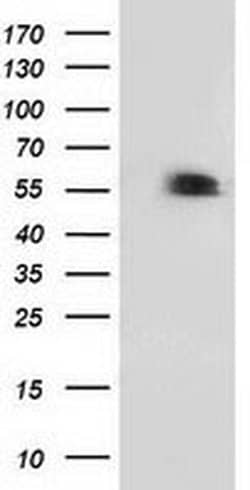

| Applications | Flow Cytometry, Immunocytochemistry, Immunofluorescence, Western Blot |